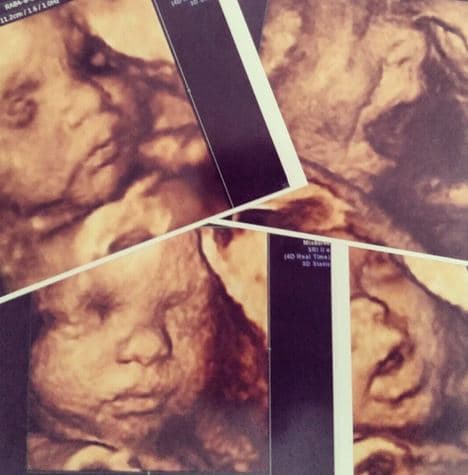

La presentadora se goza su maternidad al máximo y nos compartió su sonograma 4D.

Gredmarie, quien a sus 15 semanas de gestación, dio a conocer el sexo de su bebé durante la transmisión en vivo de Rubén & Co, vive encantada de tener una niña y por eso compartió con sus seguidores en Rubén & Co. la experiencia de ver a su bebé en un sonograma 4D.